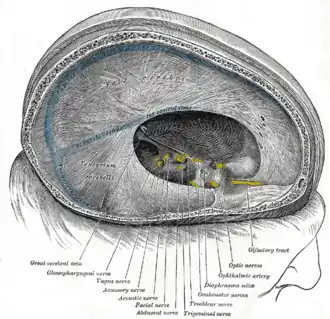

Sagittal section of the skull, showing the sinuses of the dura.

Sagittal section of the skull, showing the sinuses of the dura. -

Dura mater and its processes exposed by removing part of the right half of the skull, and the brain.

Dura mater and its processes exposed by removing part of the right half of the skull, and the brain. -